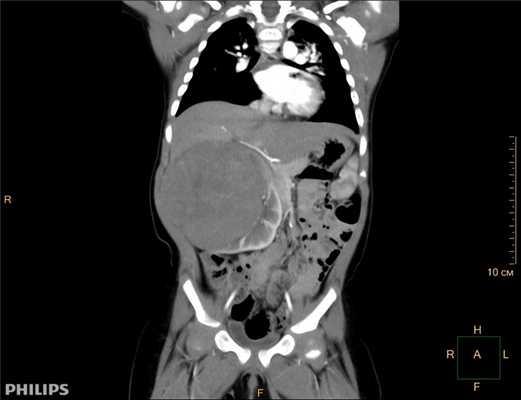

Результаты исследования: размеры плода пропорциональные, соответствуют менструальному сроку беременности. При эхокардиографии особенностей строения сердца у плода не выявлено. При оценке органов мочевыделительной системы обнаружено следующее: правая почка плода нормальных размеров и структуры. Левая почка увеличена до размеров 53х38х46 мм при 95-м процентиле нормативных для срока значений 43х24х23 мм [4] (рис. 1). В структуре почки, преимущественно в верхнем и среднем сегментах, определяется округлое образование без четких контуров, средней эхогенности, приблизительные размеры его 50х35х35 мм. При цветовом допплеровском картировании в образовании визуализируется обширная сосудистая сеть. При допплерометрии индексы сосудистой резистентности (рис. 2) в разных участках образования варьируют в широких пределах (от 0,49 до 0,77).

Рис. 1. Почки плода в режиме 2D. Видна разница в эхографической структуре. Границы почек обозначены стрелками.

Рис. 2. Режим цветового допплеровского картирования. Хорошо видны различия в характере васкуляризации нормальной почки и контрлатеральной пораженной почки.

Заключение. Беременность 32 недели. Новообразование левой почки плода (мезобластическая нефрома?).